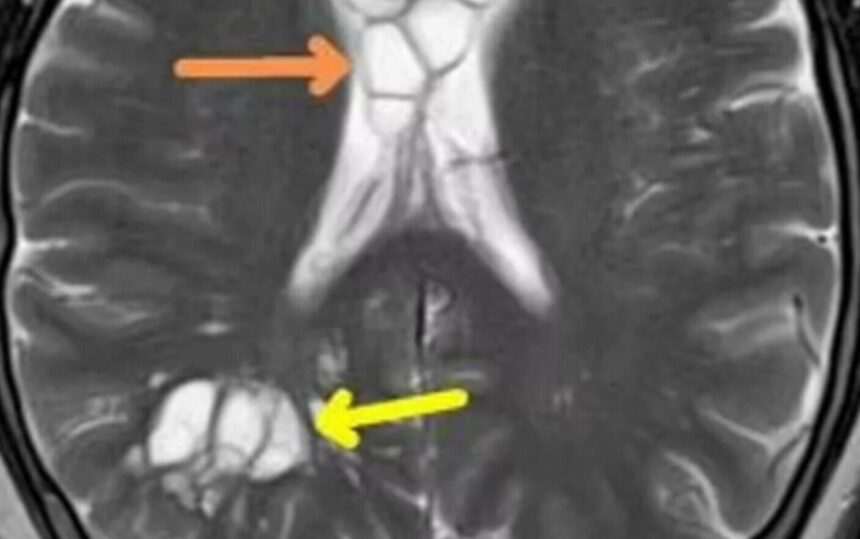

O radiografie a dezvăluit că avea multiple chisturi pe creier, precum și umflături, iar experții au confirmat că acestea erau cauzate de un tenie de porc care depusese ouă în creierul său. Ouăle cauzau iritarea țesutului de sub craniul său. Ele au fost contractate ca urmare a consumului de bacon insuficient gătit, deoarece bărbatul le-a spus doctorilor că îi placea „baconul moale”.

Condiția, cunoscută sub numele de „neurocisticercoză parazitară”, apare atunci când părți ale corpului se inflamează ca urmare a teniei de porc. Medicii presupun că parazitul a intrat în corpul său după ce a consumat alimente insuficient gătite și apoi a trecut din intestin în creier prin fluxul sanguin.